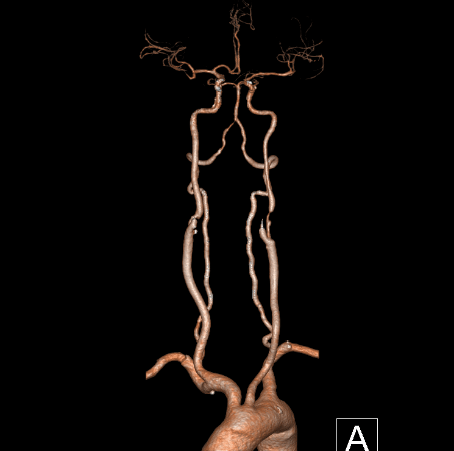

心脑联合造影

-- 右侧颈内起始部中度狭窄,经前交通向左侧代偿

-- 左侧颈内起始部重度狭窄

-- 右侧椎动脉起始部中度狭窄

-- 左侧椎基底动脉无明显异常

-- 冠脉多发狭窄